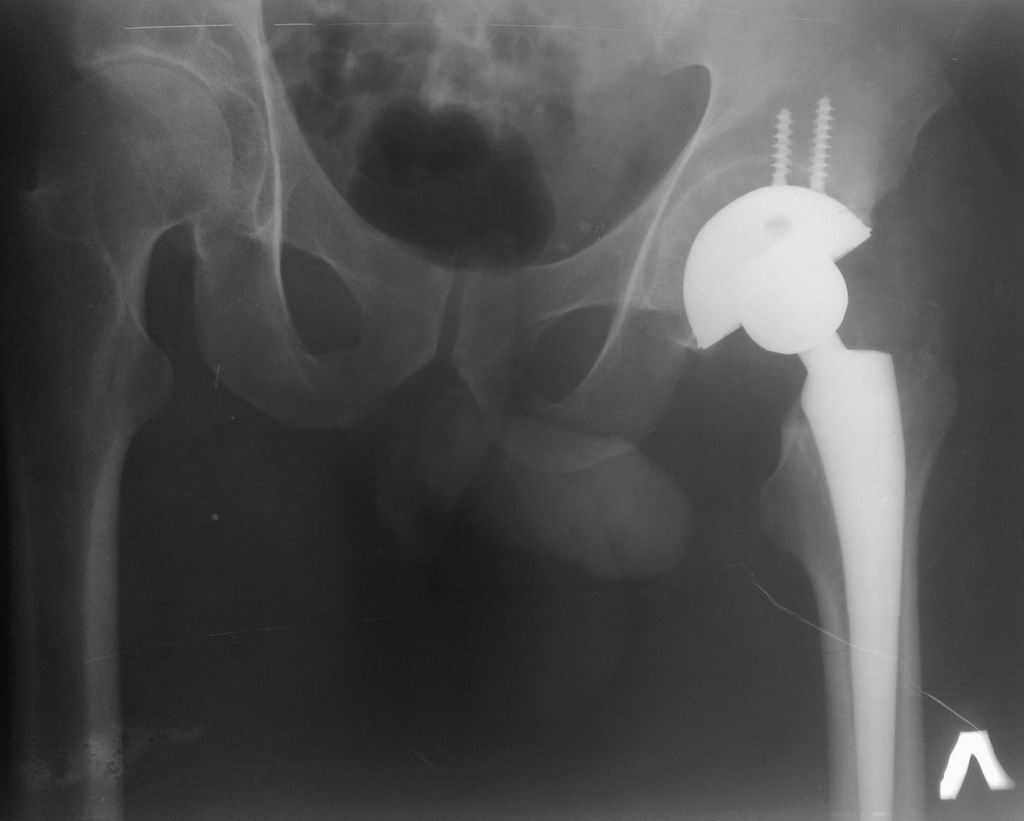

Сегодня все-таки выполнили ревизию вертлужного компонента. Действительно, чашка держалась только по окружности, относительно легко удалилась. Так что тактику считаю правильной, ибо ловить при такой установке особо нечего было. Нестабильность в блишайшее время была бы обеспечена. Снимки после переустановки в приложении. Качество, конечно не ахти какое, это сделано на столе на плохом аппарате. Посадка проконтролирована визуально через центральное отверстие. Головку не снимали, оставили короткую. Если до ревизии длина левой ноги была +1 см, то после D=S. Теперь осталось молиться, чтобы не было осложнений. Вроде бы все прошло не травматично.

01062010120.jpg

66KB (68415 bytes)